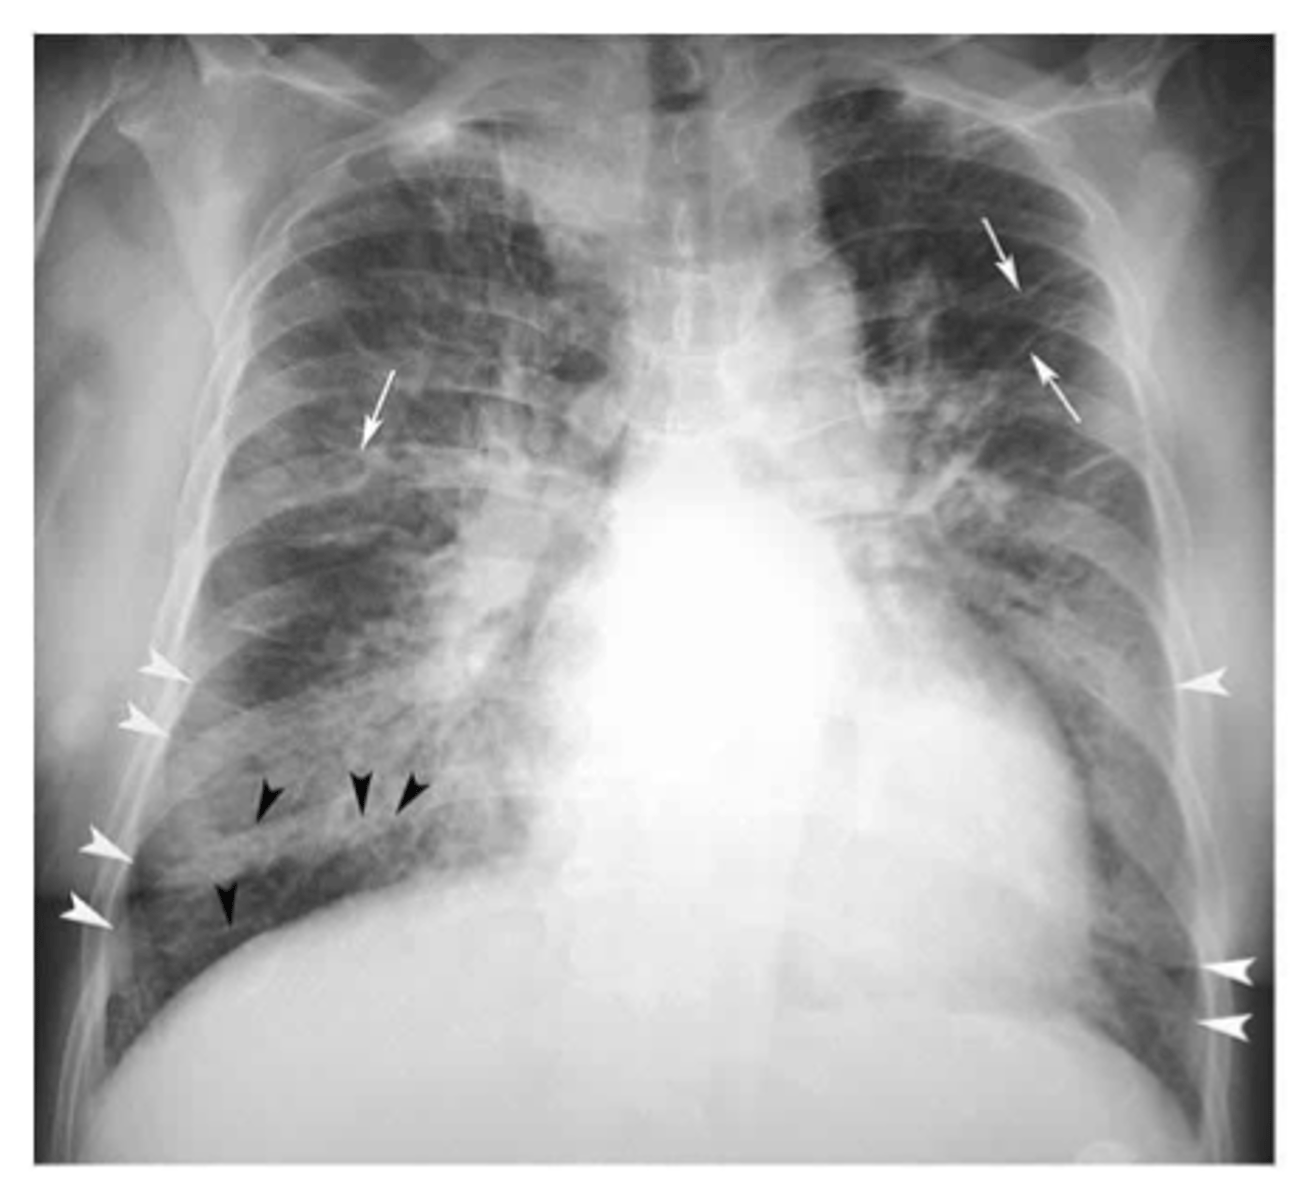

congestive heart failure

congestive heart failure